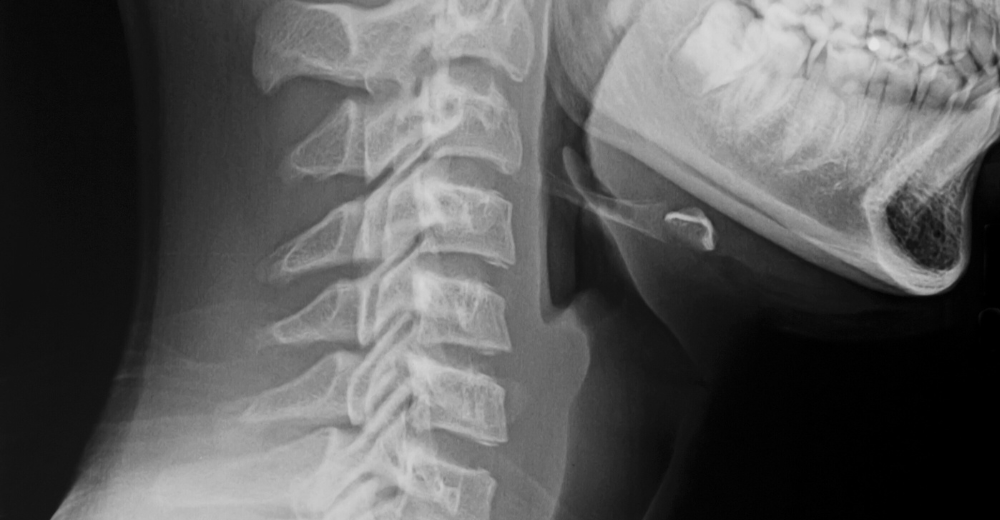

La RX Rinofaringe è un esame diagnostico non invasivo che permette di ottenere immagini dettagliate della rinofaringe, ossia la parte posteriore della cavità nasale. Presso il Poliambulatorio S-Medical Group di Sora, questo esame viene eseguito con apparecchiature all’avanguardia e da professionisti esperti, garantendo un elevato standard di sicurezza e precisione diagnostica. L’utilizzo di raggi X a bassa dose consente di individuare eventuali anomalie o patologie nella zona, aiutando i medici a definire un trattamento personalizzato.

L’acronimo “RX” si riferisce alla radiografia, mentre la rinofaringe è la parte della cavità nasale situata nella parte posteriore del naso e che si estende fino alla gola. La RX Rinofaringe è quindi una radiografia specifica utilizzata per visualizzare questa regione anatomica e diagnosticare eventuali problemi, come polipi, infezioni o malformazioni strutturali.

La RX Rinofaringe è una radiografia mirata che utilizza una bassa dose di radiazioni per creare immagini dettagliate della rinofaringe. Al Poliambulatorio S-Medical Group di Sora, l’esame si svolge in un ambiente sicuro e confortevole. Il paziente viene posizionato di fronte all’apparecchio radiologico, e il tecnico esegue l’acquisizione delle immagini in pochi minuti. Grazie alla qualità delle nostre apparecchiature, siamo in grado di fornire risultati precisi e chiari.

Grazie all’RX Rinofaringe, è possibile osservare con precisione le ossa, i tessuti molli e le strutture della rinofaringe. Al Poliambulatorio S-Medical Group di Sora, i medici analizzano attentamente le immagini per rilevare eventuali alterazioni anatomiche e anomalie, quali infiammazioni, lesioni o altre condizioni patologiche che possono influire sulla funzionalità respiratoria.